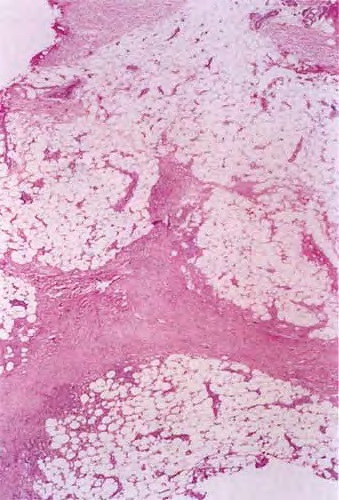

Histopathology. The histologic changes are present mainly in and near the septa of the subcutaneous tissue .

. The overlying dermis often has only a minimal to moderate, superficial and deep perivascular lymphocytic infiltrate.

In the early lesions of acute erythema nodosum, there is edema of the septa with a Iymphohistiocytic infiltrate, having a slight admixture of neutrophils and eosinophils . Focal fibrin deposition and extravasation of erythrocytes occur frequently  and can be revealed by spectral microscopy . Often, the inflammation is most intense at the periphery of the edematous septa and extends

into the periphery of the fat lobules between the individual fat cells in a lacelike fashion. Necrosis of the fat is not prominent. Rarely, clusters of neutrophils are present or the infiltrate is predominantly neutrophilic . Clusters of macrophages around small blood vessels, or a slitlike space, occur in early lesions and are known as Miescher's radial nodules . Some authors have failed to find central vessels  and have considered Miescher's nodules to be characteristic of erythema nodosum, stating that they can be found in all stages of erythema nodosum . The degree of vascular involvement is variable . Usually, there is edema of the walls of veins with separation of the muscular layers . Infiltration by lymphocytes is common, but neutrophils and eosinophils can be present as well. Necrosis of the vessel walls is very rare but has been observed in a few patients with lesions clinically indistinguishable from erythema nodosum . For example, focal vasculitis has been found in a few patients with acute erythema nodosum secondary to infections  and in a few cases of recurrent

Later lesions of acute erythema nodosum show widening of the septa, often with fibrosis and with inflammation at the edges of the septa and involving the periphery of the fat lobules . Neutrophils usually are absent, and the vascular changes are less prominent than in early lesions. There are more macrophages in the infiltrate. Macrophages at the edges of the fat lobules show phagocytosis of lipid from damaged adipocytes, and the small droplets of lipid in their cytoplasm give them a "foam cell" appearance. Granulomas formed by macrophages, without lipid deposition, are more frequent

when late lesions are compared with early ones . The granulomas often are loosely formed with macrophages predominating in a focus with multinucleated giant cells. Occasionally, well-formed, discrete sarcoidal granulomas occur in small numbers in the septa. The multinucleated cells usually have an irregular distribution of the nuclei in the cytoplasm. The oldest lesions have septal widening and fibrosis with a decrease in all of the inflammatory cells.

In chronic erythema nodosum, the histologic findings are generally similar to those of the late stages of acute erythema nodosum. However, granulomas and lipogranulomas often are more pronounced in chronic erythema nodosum. There is vascular proliferation and thickening of the endothelium with extravasation of erythrocytes . In some instances, numerous well-formed granulomas can be found and consist of epithelioid macrophages and giant cells without caseous necrosis . Although significant degrees of vasculitis have been observed by some authors , others have found vascular changes to be slight or absent . The presence of thickened fibrotic septa with marked capillary proliferation and massive granulomatous reaction have led several authors to consider erythema nodosum migrans as an entity separate from the late lesions of acute erythema nodosum . Other authors consider all of these histologic patterns to be included within the spectrum of chronic erythema nodosum .